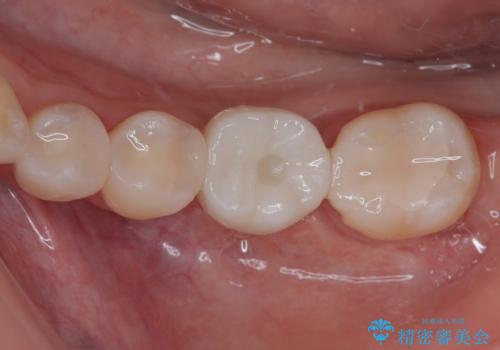

- 保険診療で治療した銀歯のやり替え希望の患者様です。

銀歯とその下の虫歯を除去し、形を整え、精度の良いシリコーンによる型どりを行いました。

セラミックインレーを接着する際は、ラバーダム防湿を行いました。

精度の高い詰め物は、二次う蝕になりにくいです。